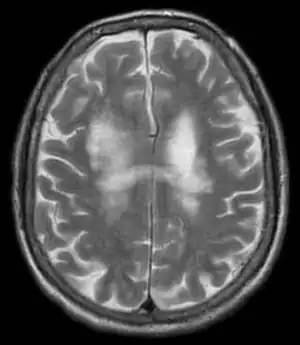

T2-weighted MRI showing progressive multifocal leukoencephalopathy

PML is diagnosed in a patient with a progressive course of the disease, finding JC virus DNA in spinal fluid together with consistent white-matter lesions on brain magnetic resonance imaging (MRI); alternatively, a brain biopsy is diagnostic[1] when the typical histopathology of demyelination, bizarre astrocytes, and enlarged oligodendroglial nuclei are present, coupled with techniques showing the presence of JC virus.[11]

Characteristic evidence of PML on brain CT scan images are multifocal, noncontrast enhancing hypodense lesions without mass effect, but MRI is far more sensitive than CT.[11] The most common area of involvement is the cortical white matter of frontal and parieto occipital lobes, but lesions may occur anywhere in the brain, such as the basal ganglia, external capsule, and posterior cranial fossa structures such as the brain stem and cerebellum.[11] Although typically multifocal, natalizumab-associated PML is often monofocal, predominantly in the frontal lobe.[11]